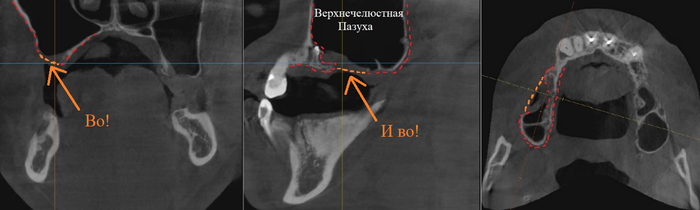

Фрагмент компьютерной томографии (вид сбоку):